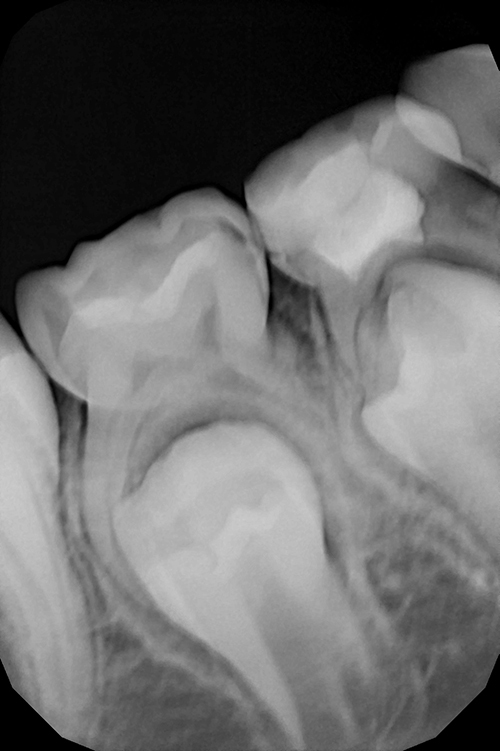

Диагностика и лечение скрытого кариеса на постоянном зубе у семилетнего ребёнка